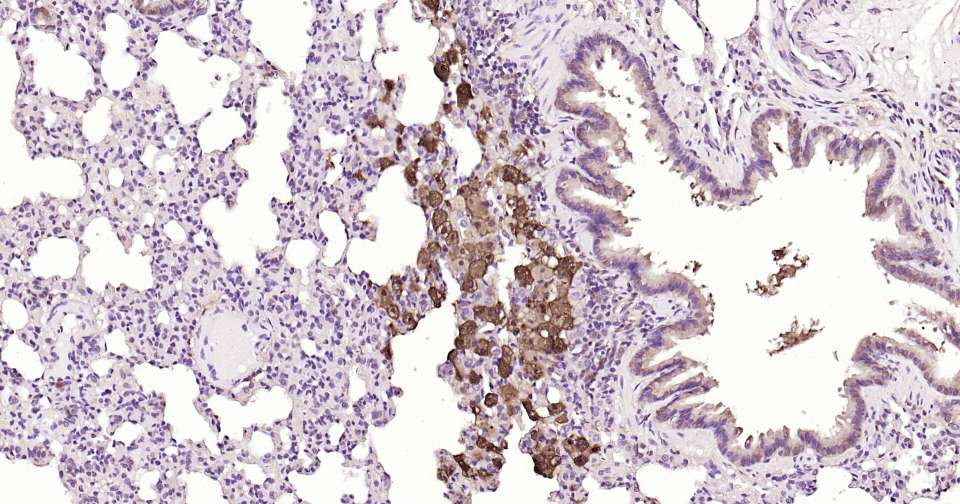

Immunohistochemical analysis of paraffin embedded mouse liver tissue slide using IHC0326 (Galectin 3 Kit).

Immunohistochemical analysis of paraffin embedded mouse lung tissue slide using IHC0326 (Galectin 3 Kit).

Immunohistochemical analysis of paraffin embedded rat liver tissue slide using IHC0326 (Galectin 3 Kit).

Immunohistochemical analysis of paraffin embedded rat lung tissue slide using IHC0326 (Galectin 3 Kit).